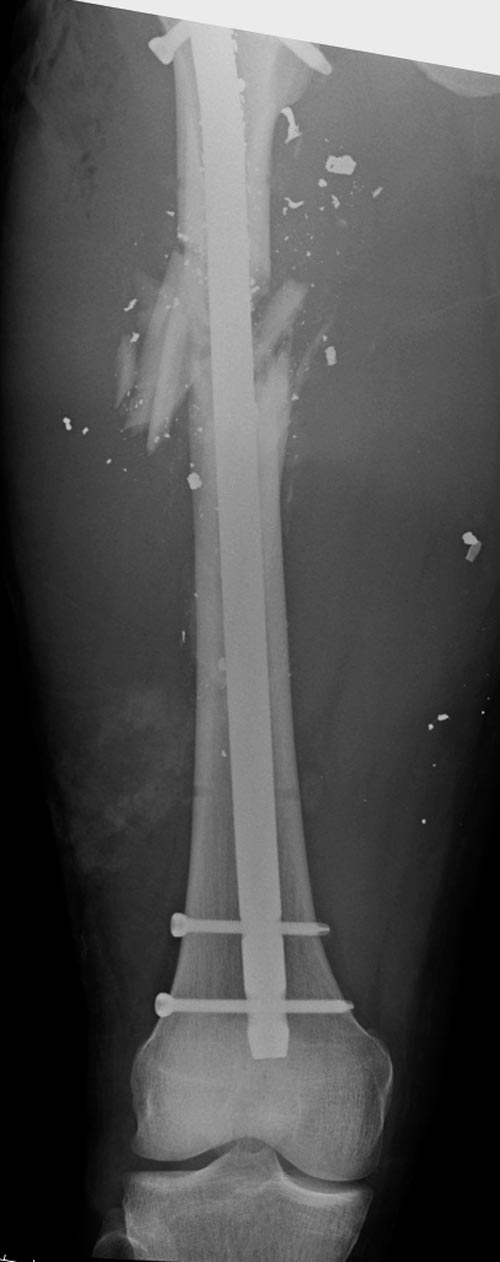

На снимках осложнение огнестрельного перелома бедра поздней инфекцией. 7

лет назад оперирован: правое бедро, сперва на ExFix, затем заменен на

гвоздь, а левая - гвоздь при поступлении.